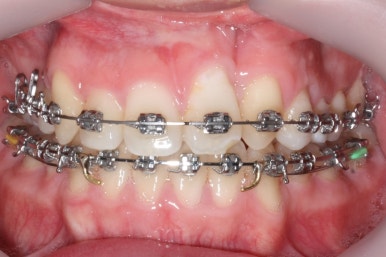

부산구순구개열 키다리아저씨치과에 처음 오셨을 때의 입 안의 모습입니다.

입천장이 갈라져서 어릴 때 봉합 수술을 했기 때문에 그 상처가 굵게 남아있는 것을 볼 수 있습니다. 일반적으로 피부상처도 다른 부위보다 단단하듯이 입천장의 봉합 상처도 매우 단단하게 아물기 때문에 성장에 방해를 주게 됩니다.

가로폭이 매우 좁고 찌그러져 있습니다.

또한 위턱이 앞으로 자라나는 것도 방해해 대부분 앞니가 거꾸로 물리게 됩니다.

또한 가랄져 있던 선에 걸쳐 있는 영구치 일부는 선천결손이 되는 경우가 많습니다.

이번 환자분도 이런 특징을 모두 갖고 계셨습니다.